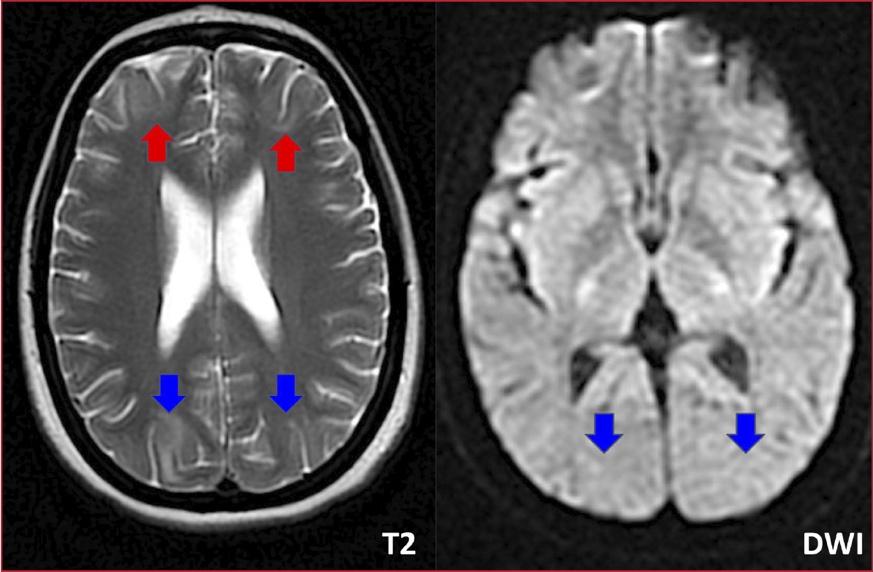

Figura 2. Resonancia magnética de cerebro.

Cambios de señal hiperintensos en secuencia T2, en la sustancia blanca

subcortical,de la región fronto-parieto-occipital, bilaterales (flechas rojas y

azules) ,con una importante reducción del edema vasogénico en comparación con

estudio previo.